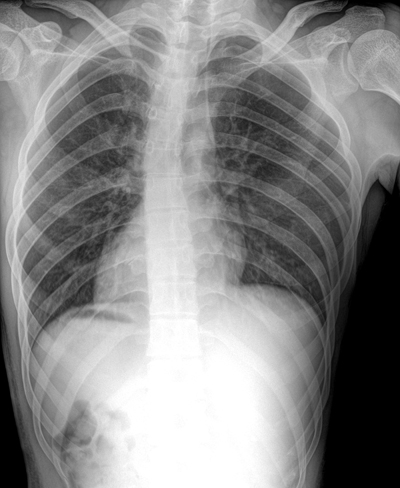

X光机的成像原理是利用X射线对不同密度的人体组织吸收不同,通过数字成像设备将X射线转化为可见的数字图像。拍胸片时需要将X光机调整到站位的姿态,被拍摄者距离X光机1.8米左右的距离,站立在摄片架前,尽量放缓呼吸,收腹,这样可以有利于拍出比较好的效果。

般在拍胸片的时候是不需要脱掉衣服的,因为衣服对X射线几乎没有吸收作用,不影响X射线的成像。如果穿的衣服很厚,建议将外套脱掉,如果衣服上有金属等饰品,建议将金属等饰品摘掉,因为他们会对X射线产生影像。